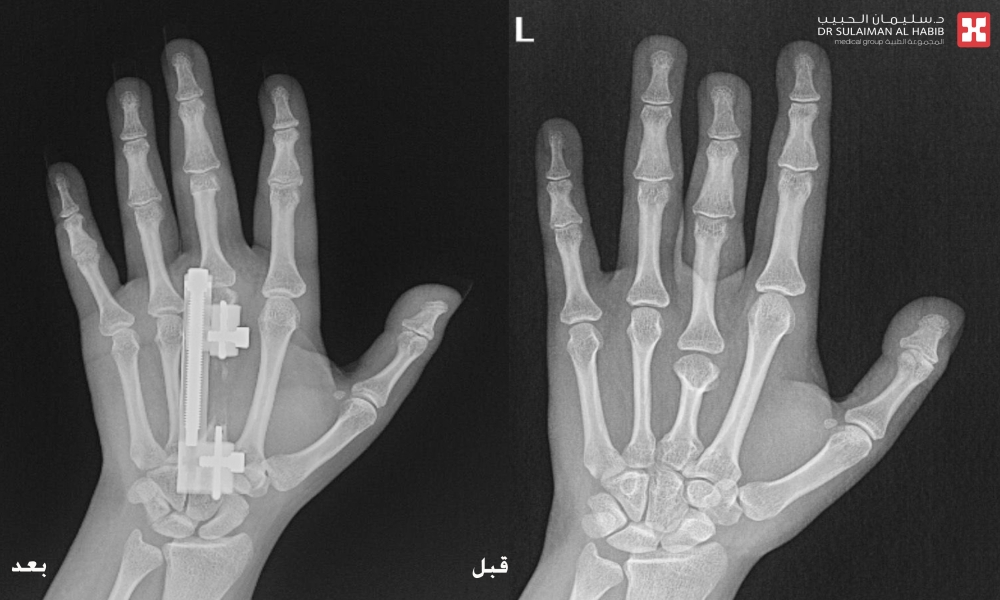

جراحة ميكروسكوبية دقيقة تُنهي معاناة عشرينية من تشوه خلقي باليدين في مستشفى الحبيب بالخبر

أنهت جراحة عظام متقدمة بمستشفى الدكتور سليمان الحبيب بالخبر، معاناة مراجعة تبلغ من العمر 24 عاماً، مع الحرج الإجتماعي، نتيجة وجود تشوه خلقي منذ الولادة أدى لإختلاف في أطوال الاصابع والإنحراف الشديد فيها، ورغم المحاولات المتكررة للعلاج في أكثر من مستشفى ومركز طبي، لم تتمكن المراجعة من إيجاد حل لمشكلتها. وظلت في رحلة بحث للعلاج لــ 10 سنوات متواصلة. ذكر ذلك الدكتور عبدالرحمن الرفاعي استشاري طب وجراحة العظام والتشوهات والحوادث وجراحات مفصل الورك المتقدمة، رئيس الفريق الطبي المعالج .

وقال د. الرفاعي أن المراجعة وصلت المستشفى في حالة نفسية معقدة، وبعد الإستماع إلى شكواها والإطلاع على ملفها الطبي، تم إخضاعها لمجموعة من الفحوصات الطبية والتي شملت، الأشعة المقطعية (C.T Scan) والسينية الرقمية (Digital X-Rays) والتحاليل المخبرية.

مشيراً إلى أن نتائج الفحوصات أوضحت وجود تشوه خلقي باليدين مع قصر بالإصبع الأوسط بأكثر من ٤ سم، بالإضافة إلى وجود ميلان وإنحسار بالحركه، وهو الأمر الذي أثر على الوظيفة الطبيعية لليد وبشكل كبير، فضلاً عن التأثير النفسي بسبب التشوه الظاهر. موضحاً أن الفريق الطبي المعالج قام بدراسة كافة النتائج، واضعاً خطة يتم فيها تطويل الإصابع.

وأوضح الدكتور الرفاعي أن العملية استغرقت ساعتين ونصف، وتم فيها استخدام تقنية التطويل والتعديل التدرجي بإستخدام جهاز Super Mini LRS ، والذي يتميز بسهولة الإستخدام، وصغر الحجم كي لا يتسبب في الإزعاج خاصة فترة الليل أو عند الحركة، نقلت بعدها المراجعة إلى جناح التنويم، للمتابعة الحثيثة، وعلى إثر تحسن حالتها خرجت من المستشفى بعد يومين وهي بصحة جيدة، مع وضع برنامج دوري لزيارة العيادة ومتابعة نتائج التطويل.

وأكد د. الرفاعي أن اليد أصبحت طبيعية تماماً من الناحية الوظيفية والشكلية ولله الحمد، مشيداً بتوفر الأجهزة والتقنيات المتقدمة لعلاج حالات التشوه العظمي، موضحاً أن حالة المراجعة، تُعد من الحالات النادره والمعقده، وذلك لوجود شبكات من الأوعية الدموية والأعصاب والأوتار المحيطة بمنطقة اليد، والتي تتطلب خبره عاليه ودقه بإجراء هذه الجراحات.